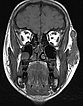

Coronal, T2-weighted fat-suppressed MRI of the face. The venous malformation typically appears very hyperintense (white).

Axial, T2-weighted fat-suppressed MRI of the face. The venous malformation appears typically very hyperintense here too. No expansion into the depth.

Coronal, T1-weighted MRI of the face. The venous malformation appears isointense to the musculature and is embedded in the surrounding fatty tissue.

Axial, T2-weighted MRI of the face (without fat suppression). The venous malformation is highly hyperintense and shows fluid-fluid levels.